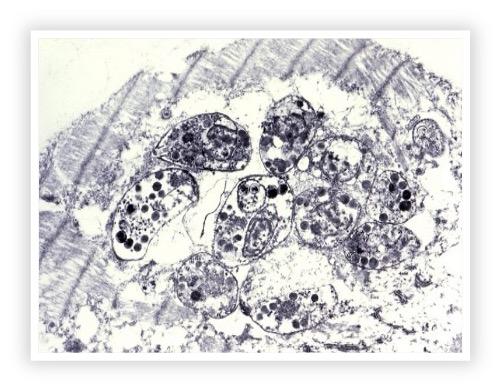

Toxoplasmose

| Name der Krankheit | Toxoplasmose |

| Erreger | Toxoplasma gondii (ein intrazellulärer Parasit) |

| Übertragung | - Aufnahme von sporulierten Oozysten aus kontaminierter Umgebung - Verzehr von rohem oder unzureichend gekochtem Fleisch, das Gewebezysten enthält |

| Inkubationszeit | 5 bis 23 Tage (abhängig vom Infektionsweg) |

| Symptome | - Fieber - Lethargie - Atembeschwerden - Husten - Muskelentzündungen - Neurologische Störungen (z. B. Ataxie, Krämpfe) - Augenentzündungen (Uveitis, Retinitis) |

| Diagnose | - Serologische Tests (Nachweis von Antikörpern) - PCR (Nachweis von T. gondii-DNA) - Histopathologische Untersuchung (bei Gewebeproben) |

| Behandlung | - Antibiotika (z. B. Clindamycin) - Unterstützende Maßnahmen je nach Symptomen (z. B. Flüssigkeitstherapie) |

| Prävention | - Vermeidung des Verzehrs von rohem Fleisch - Hygiene im Umgang mit Katzenkot (Hauptreservoir von T. gondii) |

| Anmerkungen | Toxoplasmose kann auch auf den Menschen übertragen werden, besonders gefährlich für Schwangere und immungeschwächte Personen. Hunde sind in der Regel weniger empfänglich als Katzen. |